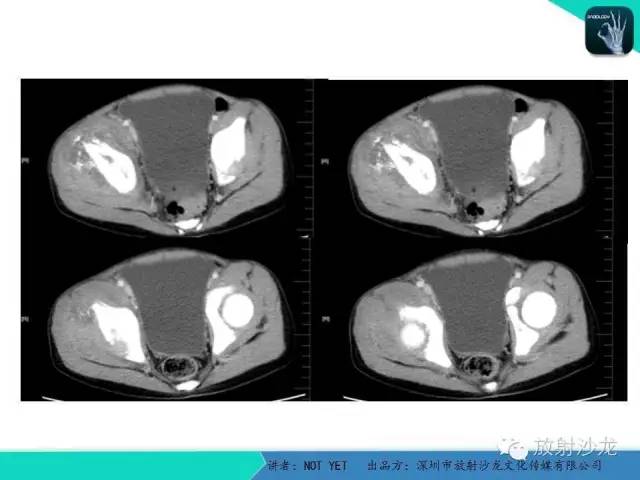

【病例】右侧髂骨Ewing肉瘤1例CT影像表现